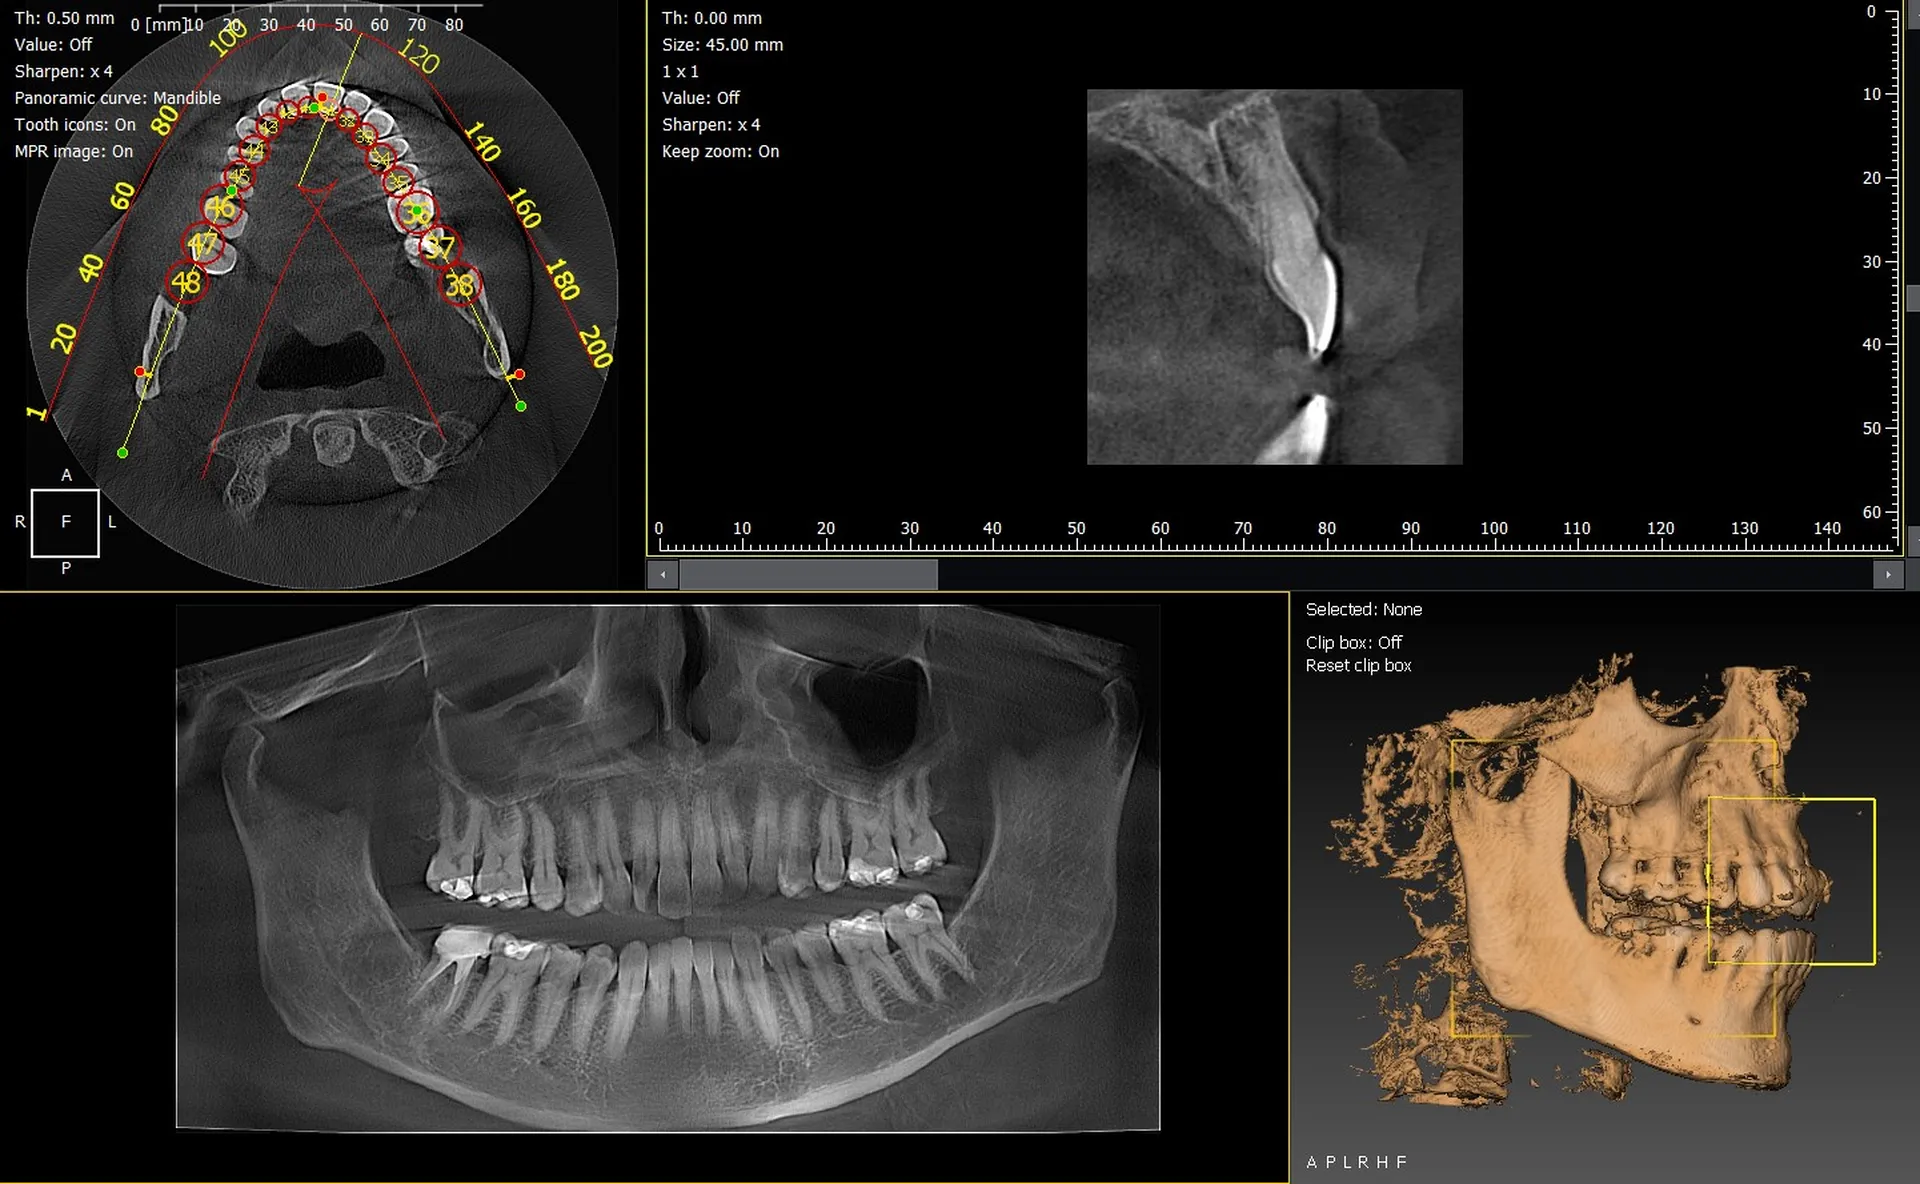

Les cabinets dentaires de Carpentras et du département du Vaucluse (84) renforcent leur plateau technique grâce à des solutions d’imagerie 3D modernes et performantes. Les panoramiques CBCT 3D VistaVox de Dürr Dental et Owandy I-Max 3D comptent parmi les équipements les plus avancés du marché, offrant une qualité d’image exceptionnelle et un diagnostic d’une grande précision.

VistaVox 3D : précision, volume optimisé et dose maîtrisée

Le VistaVox 3D se distingue par :

• un champ d’exploration adapté à la morphologie de l’arcade,

• une résolution élevée pour implantologie, endodontie et chirurgie,

• une gestion optimisée de la dose,

• un positionnement patient simple et rapide.

Owandy I-Max 3D : compact, intuitif et polyvalent

L’Owandy I-Max séduit grâce à :

• son design mural compact, idéal pour les espaces réduits,

• ses protocoles 2D/3D rapides et efficaces,

• son excellente qualité d’image,

• son interface simple et ergonomique.